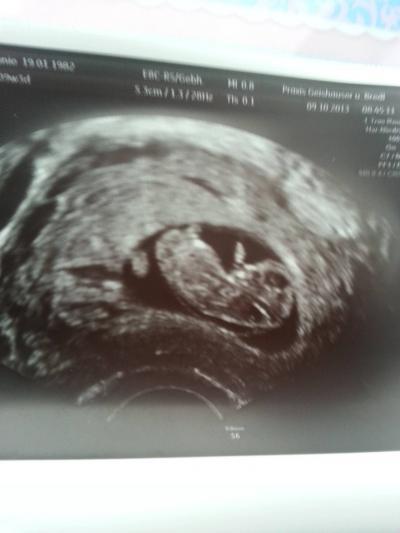

neues babyfoto:0)

Bild zu heut war arzttermin:0) - Forum für Mai - Mamis

Wow! Da kann man ja schon fast ein Profil vom Gesicht sehen! Tolles Bild :).